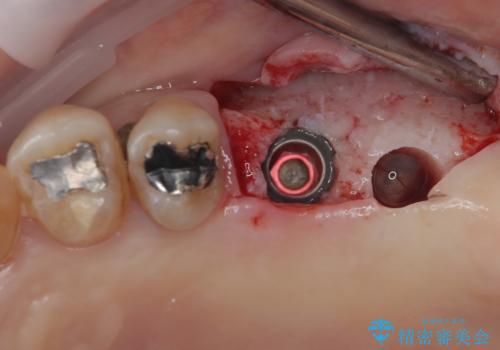

数年前まで当院でも行われていた従来の手法では、骨補填材による上顎洞底の挙上を行い、インプラント埋入に半年以上の期間を必要とするものでした。

しかしながら、ここ数年で流通してきたデンサーバーというドリルと、エキストラワイドショートインプラントの併用により、骨補填材による上顎洞底の挙上なしに埋入が行えるようになりました。

元々の骨量が少なく、通常よりは待機期間が長くなりますが、数ヶ月程度で補綴治療まで行うことができるため、こちらの手法でインプラント補綴治療を行うこととしました。